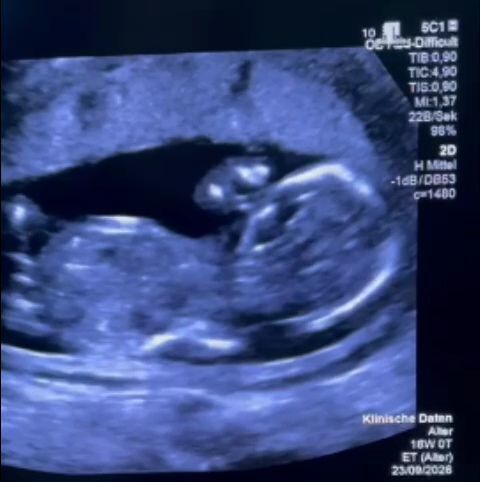

Femeia, aflată în a 12-a săptămână de sarcină, a fost diagnosticată cu o mărire a vezicii urinare a fătului. Medicii au recomandat un tratament specific, ce trebuia efectuat de urgență. Părinții au solicitat informații și au ales să efectueze intervenția la Spitalul Filantropia din București. Acolo, însă, au avut parte de un tratament descris ca fiind umilitor.

Cu toate dificultățile, familia a plecat în Germania, unde a contactat un medic specialist. Acesta a subliniat importanța intervenției rapide. Procedura a fost efectuată cu succes de un medic german, care a menționat despre o „consiliere extrem de slabă” în România. Intervenția a avut loc a doua zi după ce familia a ajuns în Germania, iar starea fătului s-a îmbunătățit.